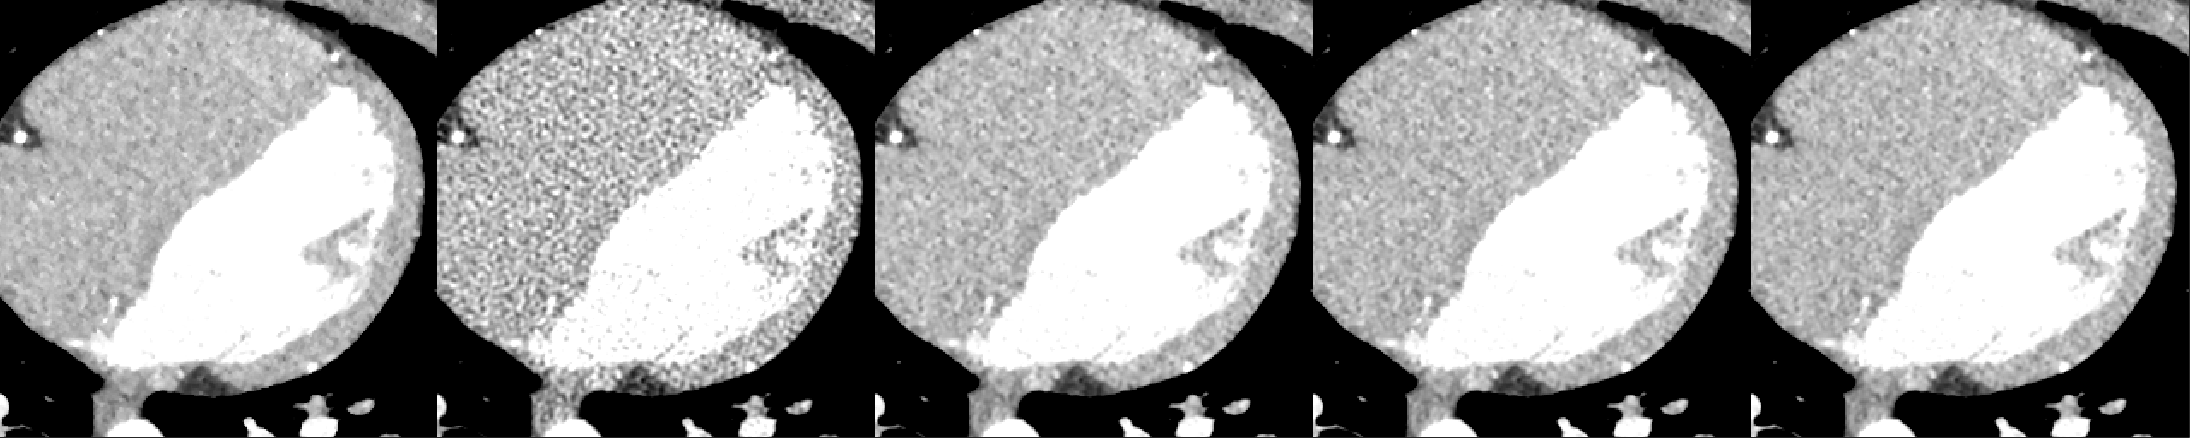

A cardiac FBP image was inferenced on the trained DL-MBIR network. Inference time for every network was between 4 and 6 seconds, and it goes up with the increase in the number of input channels. The MBIR version of the same exam was also available. Figure 3 shows a comparison, for 4 slices – LABEL:sub@fig:Image_10, LABEL:sub@fig:Image_50, LABEL:sub@fig:Image_90, and LABEL:sub@fig:Image_170 in the image volume, among MBIR image, FBP image, and the outputs of DL-MBIRZ𝐷𝐿-𝑀𝐵𝐼subscript𝑅𝑍DL\text{-}MBIR_{Z}, where Z=1, 3, 5𝑍135Z=1,\ 3,\ 5. Figure 4 shows a comparison, for the same slices in the image volume, among difference between images and the MBIR images. Figure 5 has a profile plot to show the comparison of DL-MBIRZ𝐷𝐿-𝑀𝐵𝐼subscript𝑅𝑍DL\text{-}MBIR_{Z} and FBP images w.r.t the MBIR images.

Refer to caption

(a)

(b)

Figure 5: Image profile. LABEL:sub@fig:Image_160_yline One axial slice, from left to right, of: MBIR𝑀𝐵𝐼𝑅MBIR, FBP𝐹𝐵𝑃FBP, DL-MBIR1𝐷𝐿-𝑀𝐵𝐼subscript𝑅1DL\text{-}MBIR_{1}, DL-MBIR3𝐷𝐿-𝑀𝐵𝐼subscript𝑅3DL\text{-}MBIR_{3}, DL-MBIR5𝐷𝐿-𝑀𝐵𝐼subscript𝑅5DL\text{-}MBIR_{5} LABEL:sub@fig:Profile_160 Profile plot of the images along the yellow line.

Visually, all DL-MBIR images bear close resemblance to the MBIR images in figure 3. It is confirmed by the difference images in figure 4. In the profile plot of Figure 5, the DL-MBIR profiles closely follow that of MBIR.